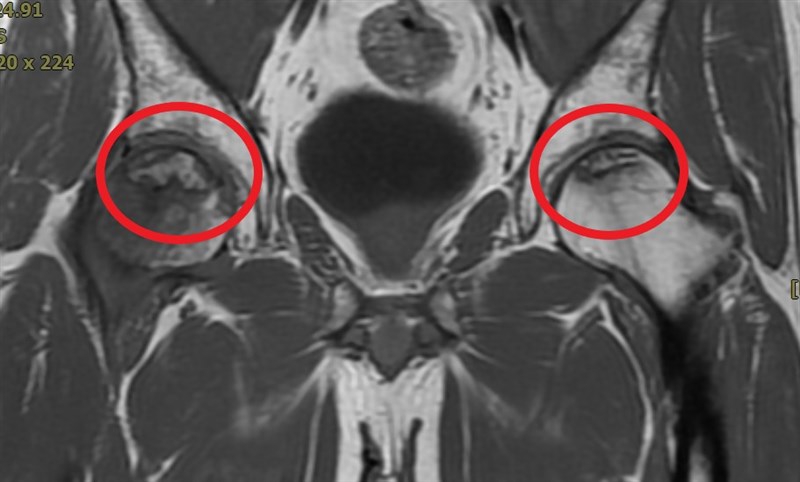

貪杯男子飲酒過量造成髖關節卡卡,走路彷彿機器人,經以水介質震波治療改善局部血流供應,延緩骨壞死速度,有助於緩解痠痛。圖/活力得中山脊椎外科醫院提供

「活力得中山脊椎外科醫院」院長楊椒喬今天指出,患者自述雙側臀部及髖部走路時痠痛難熬,又右側較左側嚴重。醫院診斷發現男子雙側髖部在活動時卡卡,因此安排核磁共振檢查,確診為雙側髖關節股骨頭缺血性壞死。